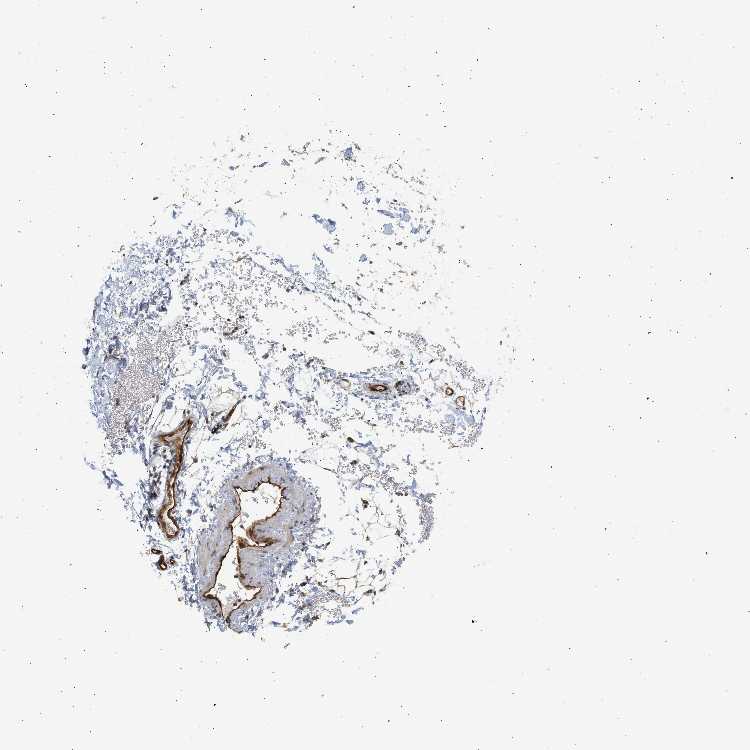

SOFT TISSUE 2 - Antibody stainingi

Antibody staining in the annotated cell types in the current human tissue is reported as not detected, low, medium, or high, based on conventional immunohistochemistry profiling in selected tissues. This score is based on the combination of the staining intensity and fraction of stained cells.

Each image is clickable and will lead to virtual microscopy that enables deeper exploration of all samples and also displays staining intensity scores, fraction scores and subcellular localization as well as patient and tissue information for each sample.

Antibody HPA017959Antibody HPA030549

Fibroblasts Not detectedHigh

Peripheral nerve Not detectedNot detected